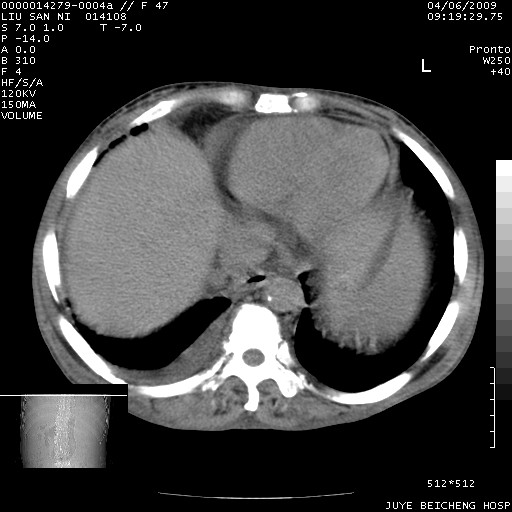

以下是引用前行在2009-4-7 10:31:00的发言:[br]肝脾肿大;双肾增大,双肾盂少量积水可能,肾膜膜增厚,肾周间隙增宽,并见桥间隔,提示结缔组系统疾病、系统性红瘢狼疮肾可能性大。继发右侧胸腔、心包、腹腔积液。